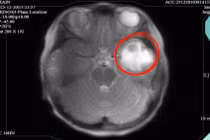

Từ khóa: Chẩn đoán và điều trị áp xe não ở trẻ em